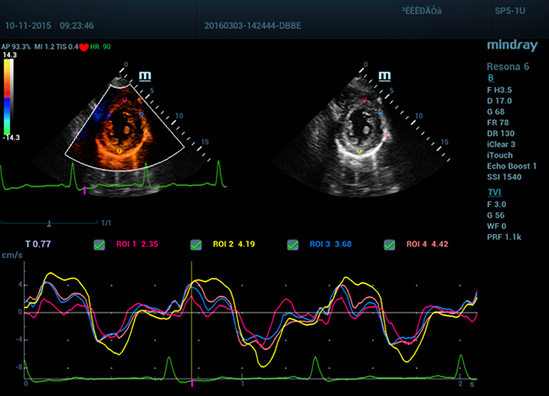

• 12 TDI QA

Авто IMT (толщина интимы-медии)